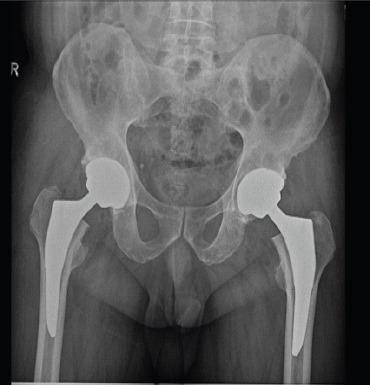

Case report: This case study relates the history of a 56-year-old man with ankylosing spondylitis who underwent bilateral THA using a CoC articulations. Initially asymptomatic for 4 years, he developed pain, swelling around the right hip, and his imaging showed extensive osteolysis with pseudotumor formation. His fine-needle aspiration cytology report was inconclusive, so he underwent stage 1 procedure that is removal of prosthesis and biopsy. His histopathology report confirmed pseudotumor formation with presence of fibrin, proliferating fibroblasts, hemosiderin-laden macrophages and lymphocytes. Since the patient was not keen on second stage revision arthroplasty, he was mobilized with heel and sole raise and walking aid.

Conclusion: Pseudotumor formation occurred without any damage to ceramic head and liner, without any malposition of components, with no impingement between components and normal metal ion levels in our case. This case report further strengthen existing literature about pseudotumor formation in CoC articulation. Further studies needed to know exact tribology and individual immune response for ceramic wear debris.